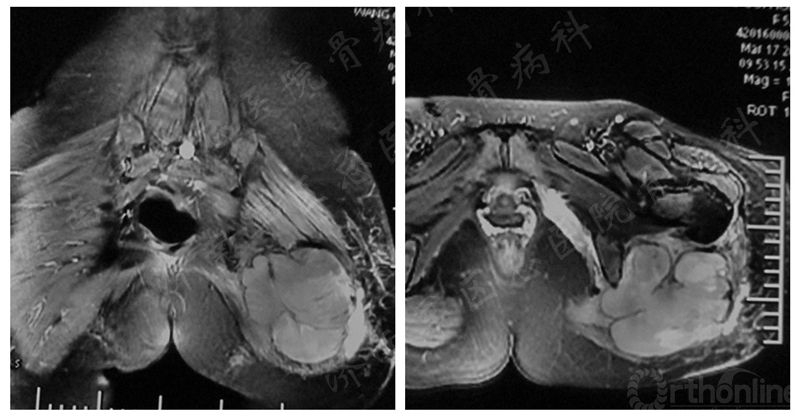

患者女性,53岁。患者于2016-1-14查骨盆MR,结果显示左侧髋关节后方,外旋肌群内T1低信号软组织肿块影;左侧髋关节后方,外旋肌群内T2高信号软组织肿块影。

术前MRI